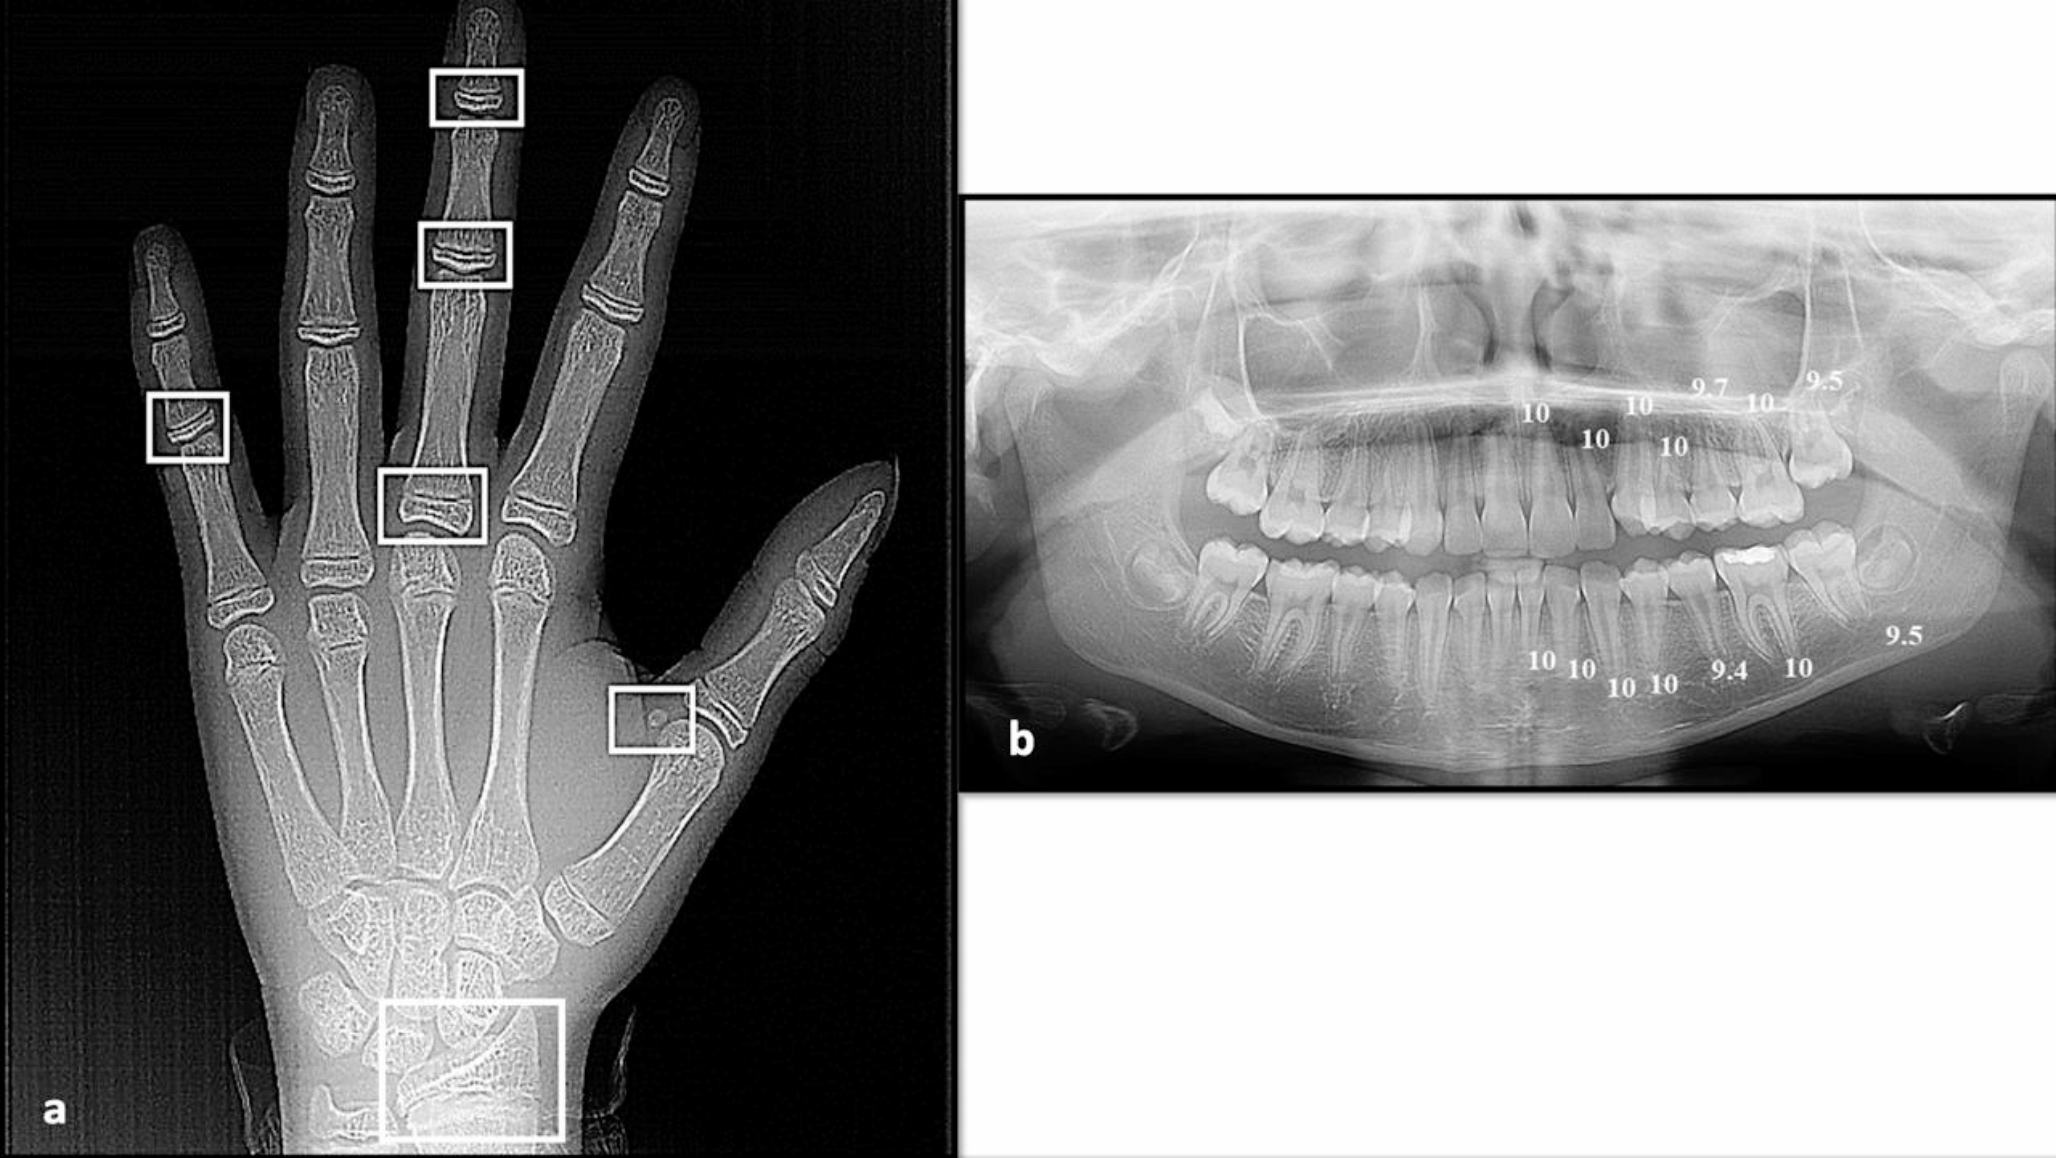

Panoramic images were processed by a computer-aided drafting program (Adobe Photoshop CS, Adobe Systems Incorporated, San Jose, CA, USA) and then matched as closely as possible with the comparative figure of Nolla. The development of the seven left permanent maxillary and mandibular teeth, excluding the third molar, was scored as ‘0’ for the absence of crown, and ‘1’ to ‘10’, depending on the stage of calcification where the stage 10 illustrates that mineralization at the apical end of the root is completed. The sum of stages for 14 maxillary and mandibular teeth for each participant was assigned as Nolla score and graded as (A to H) for males and (a to h) for females using the corresponding tables described by Nolla [36]. Then, the total sum was matched to the average sum for males or females to translate the developmental value into the dental age. Figures 1, 2 and 3 depict the chronological age assessment in three children, showing different skeletal, dental and chronological ages.

Fig. 1

a) Hand-wrist X-ray of a 13.22-year female patient showing different sites (in white) of skeletal maturity indicators (SMI) assessed by Fishman method; capping of epiphyses of the middle phalanx on the fifth finger (SMI = 7), and skeletal age is 12.51 years, b) Panoramic X-ray of the same patient showed different scoring of dental development of the mandibular and maxillary teeth on the left side (except the third molar), marked according to the Nolla method; the total scoring was 138.1 and the calculated dental age was 13 years

Bild vergrößern